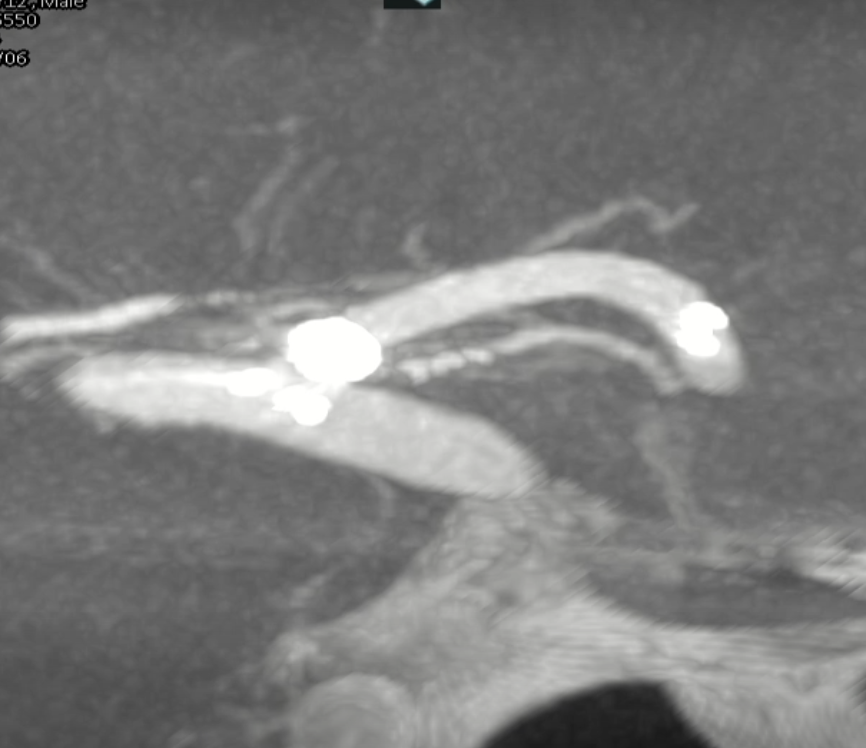

术前外院 DSA 2025-02

箭头所指右侧A1微小动脉瘤

工作位正位造影(图片)

工作位侧位造影(图片)